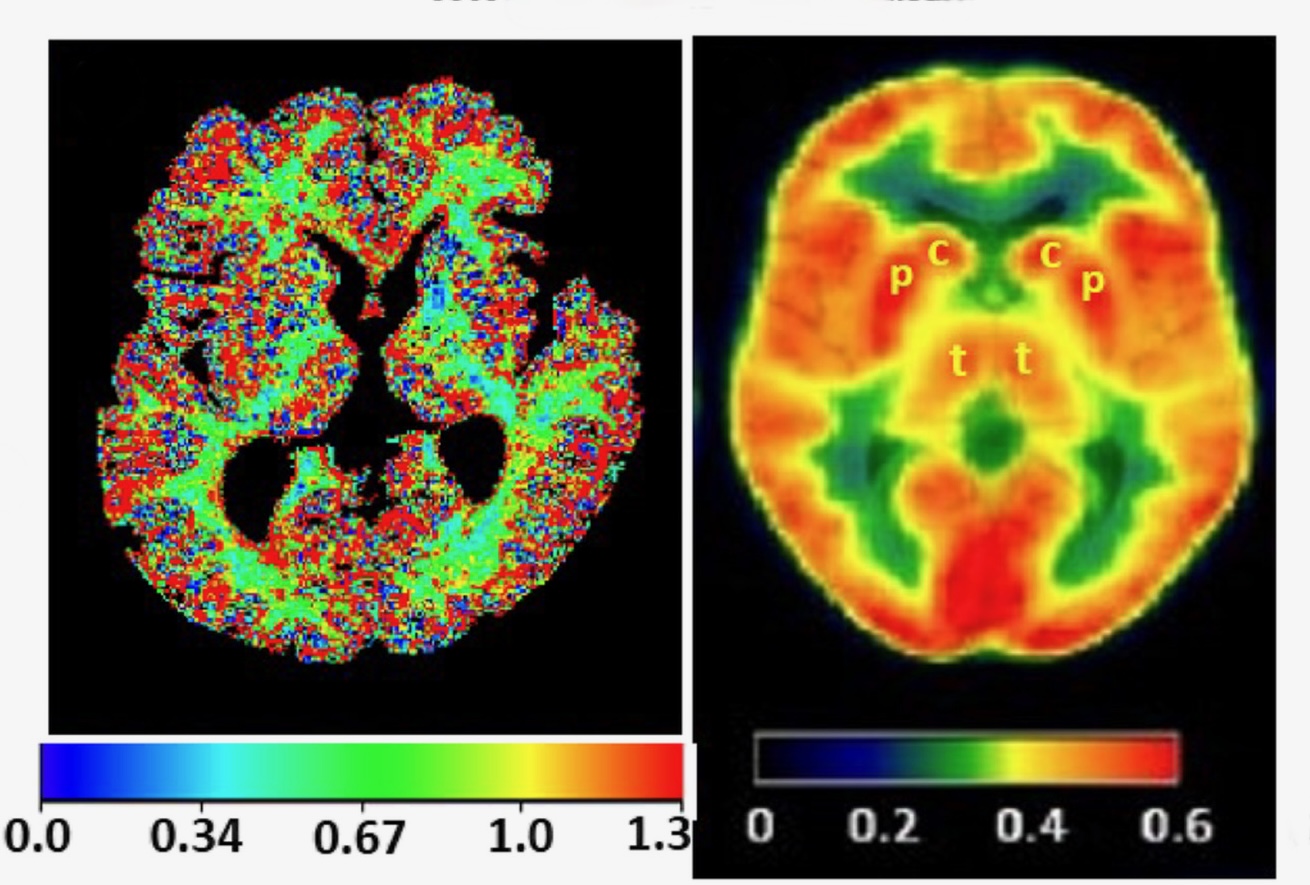

To survive, every cell in the body puts enormous energy into sustaining the right balance of water and essential electrolytes. Researchers at Oregon Health & Science University have developed a way to use magnetic resonance imaging, or MRI, to map this activity in fine detail in the human brain and other organs.

The innovation — called metabolic activity diffusion imaging, or MADI — is opening up new possibilities for detecting cancers and revealing if a tumor is responding to treatment. “MADI is a new way to make images of metabolic activity within organs and tissues at high spatial resolution, and it’s totally noninvasive,” said inventor Charles Springer, Ph.D. “In principle, this method could apply to almost any pathology.” Full article